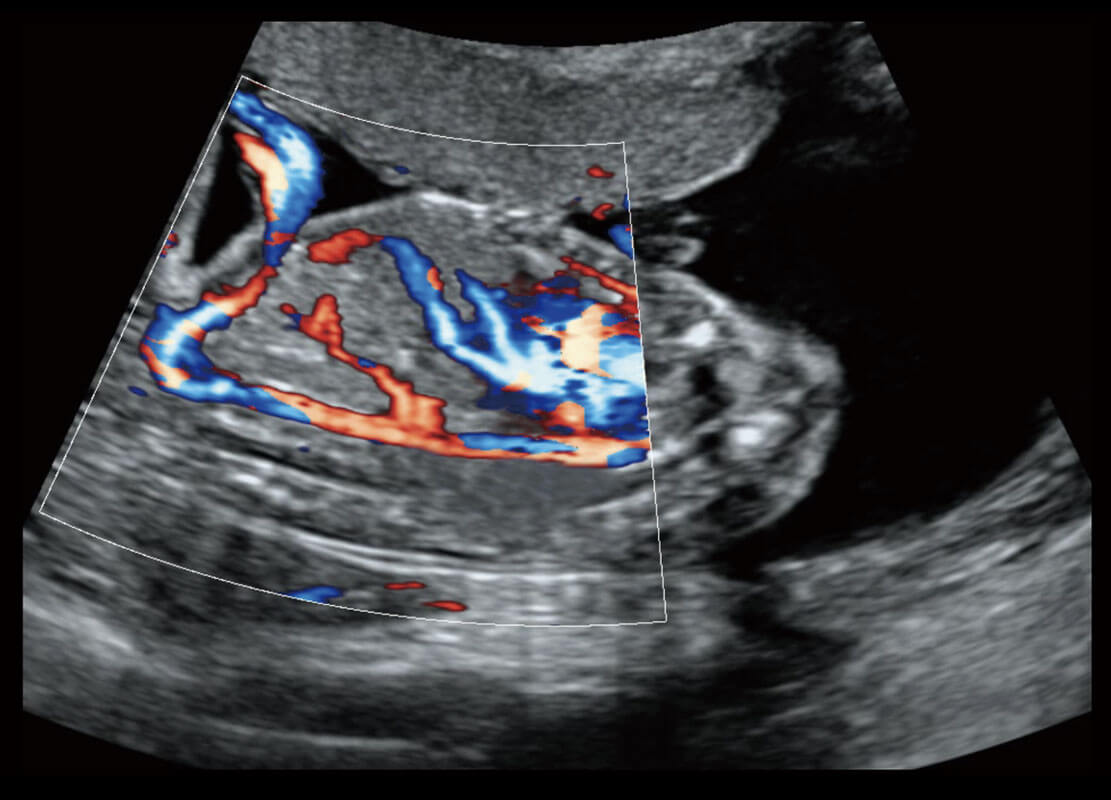

胎心筛查

P60搭载一系列胎儿心脏成像技术,实现精细的胎儿心脏评估。

• 四腔心血流

• 右室双出口